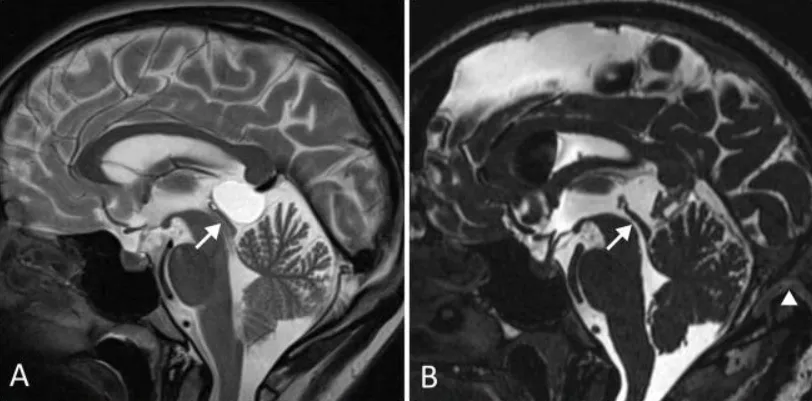

术前(A)及术后(B)正中矢状位MRCISS成像显示:松果体囊肿导致中脑导水管狭窄(箭头标示),但未引发脑积水。术后影像(B)证实囊肿完全切除,中脑导水管恢复通畅。开颅手术范围延伸至横窦区域(箭头标示)。患者临床症状完全消失。手术入路选择基于增强T1加权磁共振成像(冠状位D、E,轴位F)评估:左侧优势静脉窦及桥静脉分布情况,最终选择静脉窦穹隆较高的右侧入路。小脑幕倾斜度分析表明:旁正中入路(G)至松果体区的视角轨迹较中线入路(H)更为平缓。